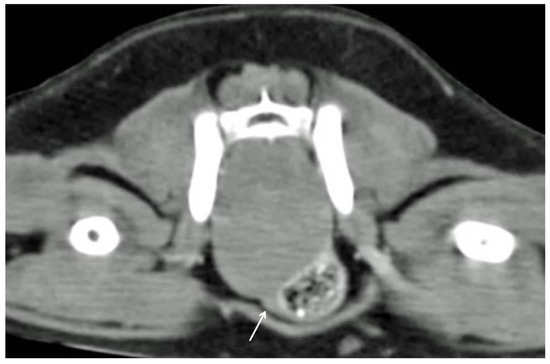

Computed tomography revealed the presence of a single and 2 adjacent masses in 6 out of 7 (86%) (n 3–5, 9–11) and 1 out of 7 cases (14%) (n 8), respectively. The masses appeared well defined and homogeneous, with mild contrast enhancement in all cases. Colonic and rectal displacement, and urethral compression were always present (Figure 1).

Figure 1. Tomographic appearance of a intra-pelvic mass. The colon is displaced ventrolaterally. The urethra is highlighted by the white arrow.